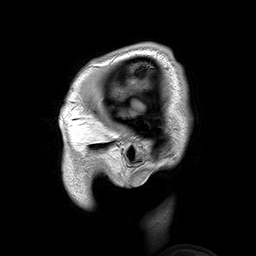

Animation of a stack of vertical MRI sections of a normal adult human brain

An MRI of a male's head showing benign familial macrocephaly (head circumference > 60 cm)

Recently, the boundaries between various specialties have blurred, as they are all influenced by basic research in neuroscience. For example, brain imaging enables objective biological insight into mental illnesses, which can lead to faster diagnosis, more accurate prognosis, and improved monitoring of patient progress over time.[54]